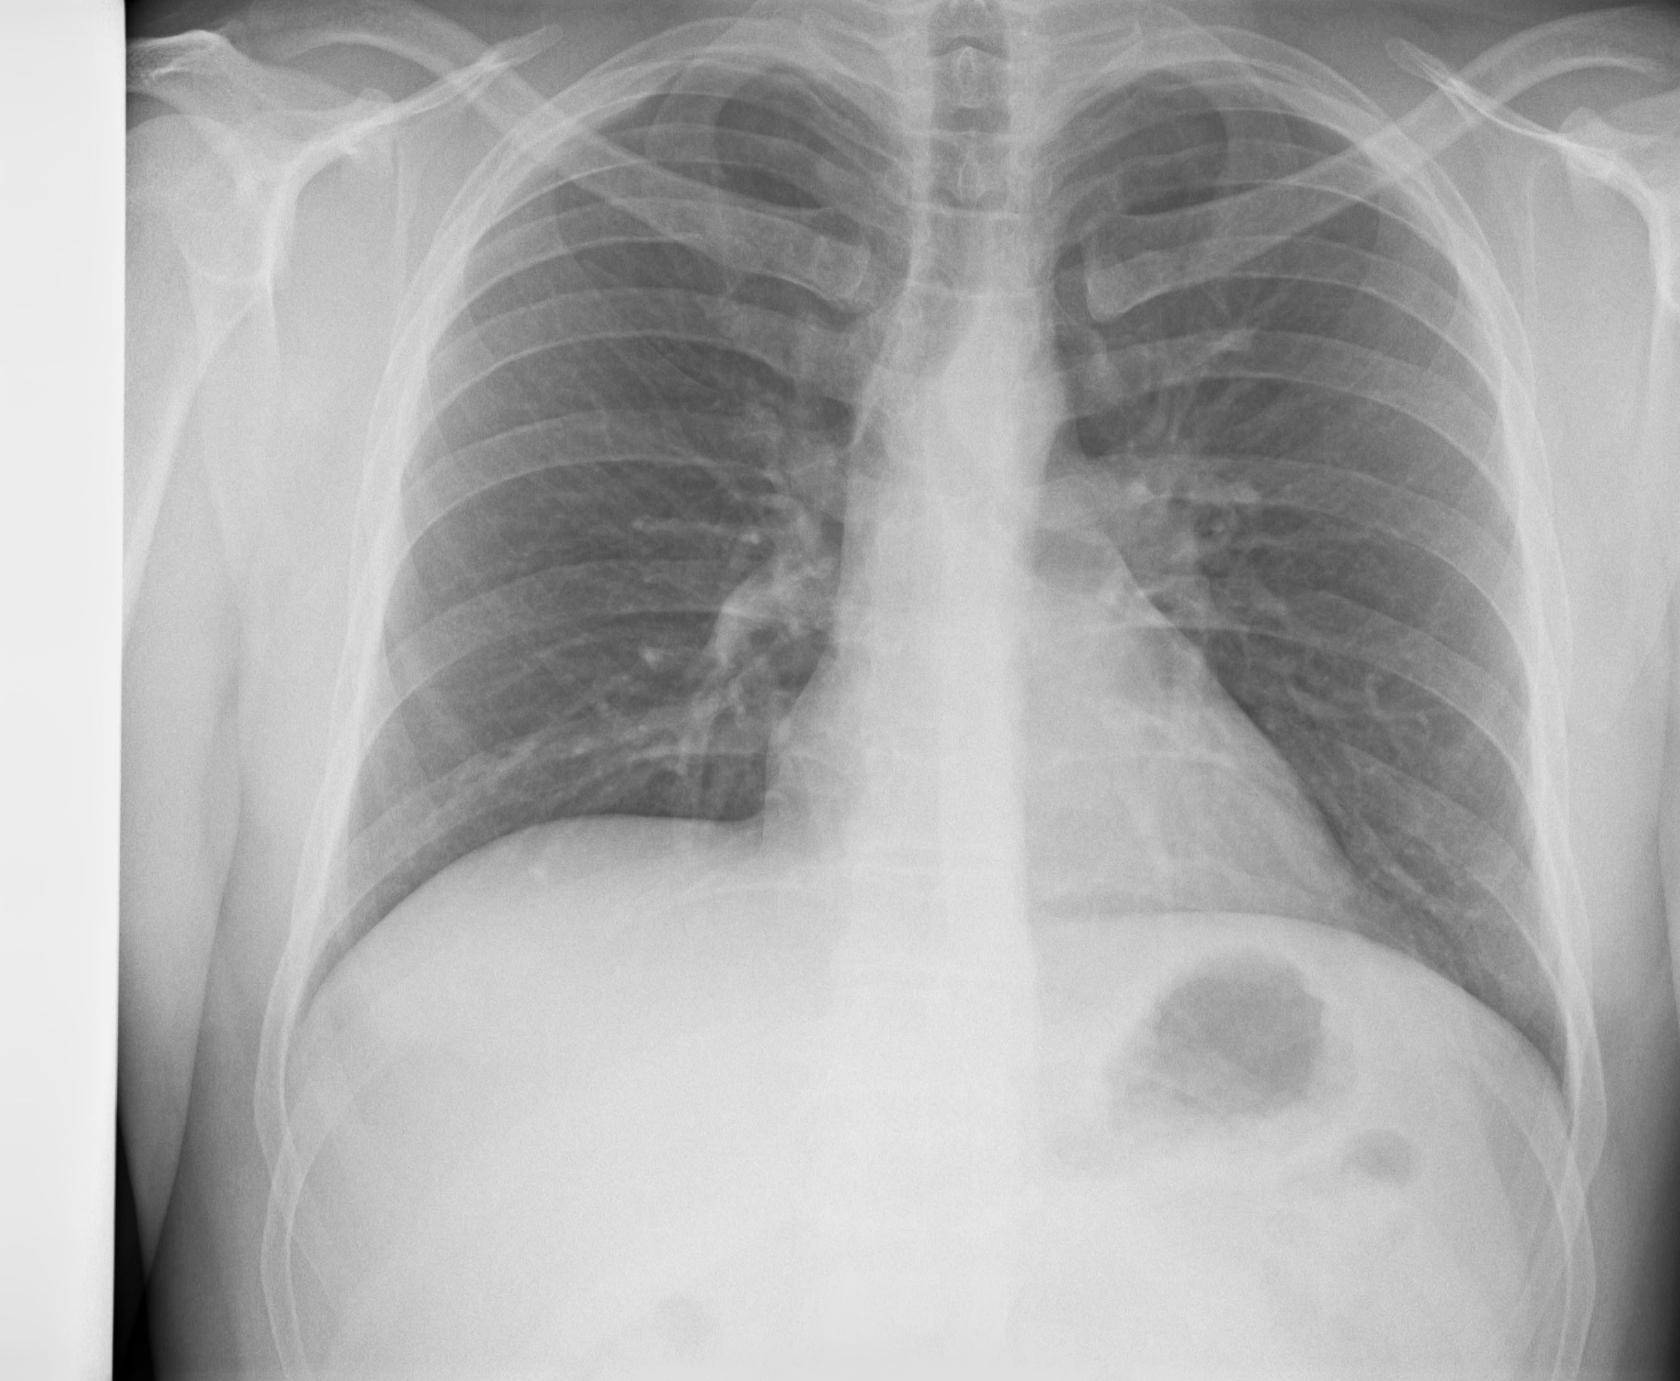

Снимок грудной клетки здорового ребенка: примеры и диагностика

Раздел: Мудрость в объективе